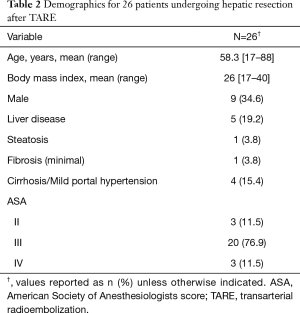

Twenty six patients underwent neoadjuvant lobar TARE prior to major hepatic resection during the study period. Most patients (n=17) underwent liver resection between 2016 and 2018. Patient demographics are summarized in Table 2. Five patients underwent percutaneous liver biopsy prior to intervention. Of these, four patients with hepatocellular carcinoma demonstrated signs of cirrhosis and one patient with cholangiocarcinoma demonstrated steatosis and minimal portal fibrosis (Table 2). The indications for TARE were: inadequate FLR volume for resection (n=19, 73.1%), prior failed PVE (n=4, 15.4%), downstaging for potential orthotopic liver transplantation (n=1, 3.8%), symptom control from tumor (n=1, 3.8%), and recent myocardial infarction with stent placement (n=1, 3.8%). Approximately 85% (n=22) of patients also had high risk tumor biology, per multidisciplinary consensus, that would benefit from a biologic test of time. The majority (n=20, 76.9%) of patients had pre-operative Albumin-Bilirubin grades of A1 or A2 with a median tumor size of 6.7 cm (3.7–10.2 cm). Tumors were right sided, bilobar, or central in 20 (76.9%), 5 (19.2%), and 1 (3.8%) patients, respectively. Eighteen patients (69.2%) had solitary tumors. Glass and resin microspheres were used in 21 (80.8%) and 5 (19.2%) patients, respectively. Repeat TARE was performed on 2 (7.7%) patients in the setting of large (>10 cm) primary tumors with partial response to initial TARE. PVE was performed in 6 (23.1%) patients after TARE. Four (15.4%) patients underwent prior liver directed intra-arterial therapy with chemoembolization (n=3, 11.5%) or bland embolization (n=1, 3.8%) for lesions in the same hepatic lobe subsequently salvaged with TARE. Nineteen (73.1%) patients received concurrent systemic therapy including 5FU based regiments (n=7, 26.9%), Gemcitabine/Cisplatinum (n=6, 23.1%), Sorafenib (n=3, 11.5%), octreotide analogue (n=2, 7.7%), and immunotherapy (n=1, 3.8%).